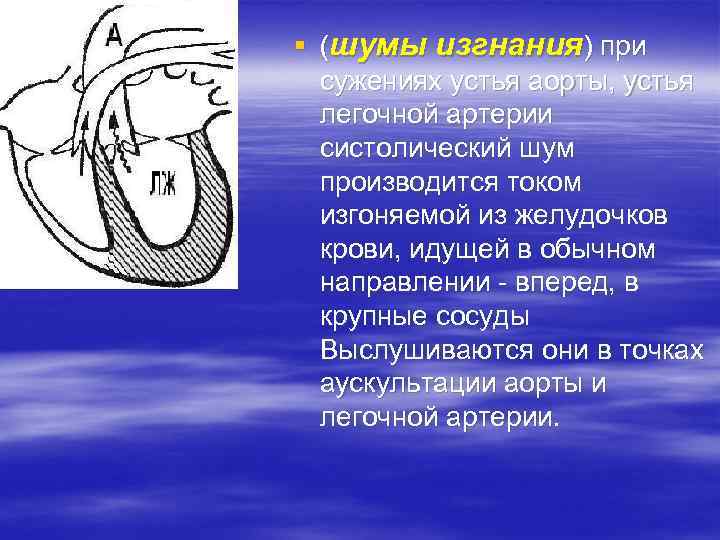

§ (шумы изгнания) при сужениях устья аорты, устья легочной артерии систолический шум производится током изгоняемой из желудочков крови, идущей в обычном направлении - вперед, в крупные сосуды Выслушиваются они в точках аускультации аорты и легочной артерии.

§ (шумы изгнания) при сужениях устья аорты, устья легочной артерии систолический шум производится током изгоняемой из желудочков крови, идущей в обычном направлении - вперед, в крупные сосуды Выслушиваются они в точках аускультации аорты и легочной артерии.